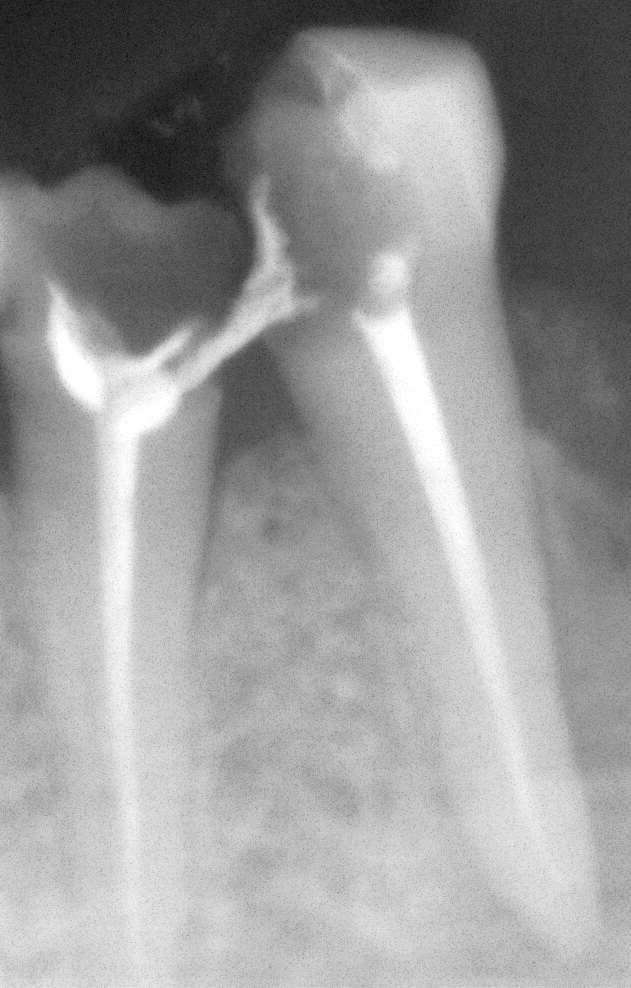

RE-TREATMENT ROOT CANAL CASE OF ANTERIOR

TEETH (FRONT TEETH)

ROOT CANAL DONE BY GERMAN DENTIST FAILED (IMPROPER ROOT CANAL OBTURATION)

Re treatment of the same done at cheema dental

Before After